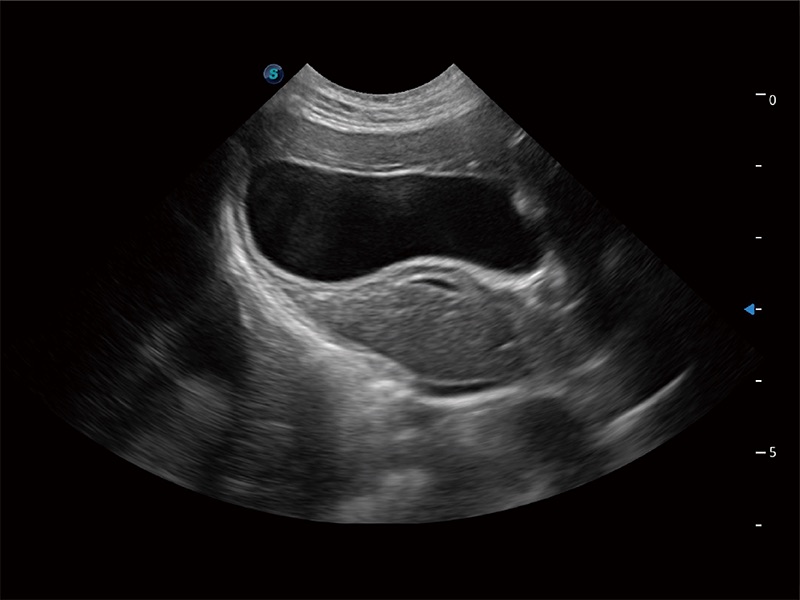

优异的基础图像

ProPet 80 全新的动物超声智能软件和丰富的探头群,为动物医生提供了高清晰度和精细分辨率的图像,无论在宠物、马科、畜牧还是实验室动物等应用中都可以轻松应对,为您的日常工作带来满意的体验。

(犬)胎儿四腔心